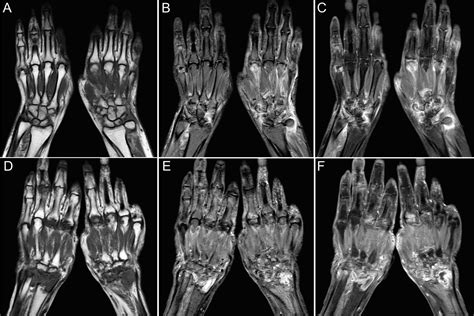

Understanding the intricacies of an MRI of hand can provide valuable insights into various hand conditions and injuries. Magnetic Resonance Imaging (MRI) is a powerful diagnostic tool that uses magnetic fields and radio waves to produce detailed images of the body's internal structures. When it comes to the hand, MRI scans offer a non-invasive way to visualize bones, muscles, tendons, ligaments, and other soft tissues with exceptional clarity.

An MRI of hand is a specialized imaging technique that focuses on the structures within the hand. This procedure is particularly useful for diagnosing conditions that affect the bones, joints, and soft tissues of the hand. Unlike X-rays, which primarily show bone structures, an MRI provides a comprehensive view of both hard and soft tissues, making it an invaluable tool for orthopedic and rheumatologic evaluations.

• Detailed Images: MRI provides high-resolution images of both hard and soft tissues, allowing for a comprehensive evaluation.

• Versatile: MRI can be used to diagnose a wide range of conditions, from bone injuries to soft tissue abnormalities.

• Accurate Diagnosis: The detailed images help in making an accurate diagnosis, which is crucial for effective treatment planning.